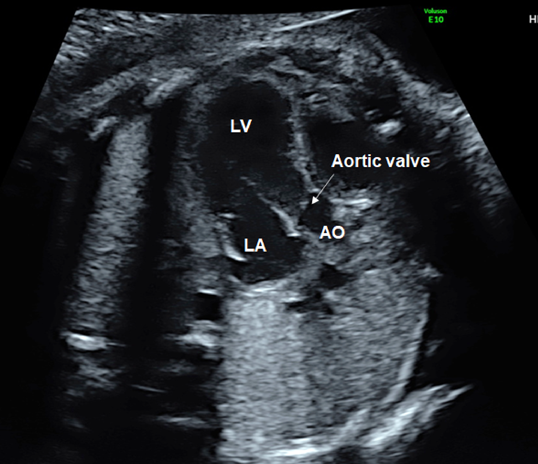

(4) Observation of Outflow Tracts

Tilting the probe toward the head of the fetus during the 4CV gives a view of the ventricular outflow tracts (Fig. 7). The left ventricular outflow tract (the aorta does not branch immediately after originating from the ventricle) is visualized first (Fig. 10), then the right ventricular outflow tract (the pulmonary artery branches immediately after originating from the ventricle) with further tilting (Fig. 11). The whole picture of the major vessels and their connections to the ventricles can be seen in the long-axis view. The normal features of the outflow tracts are; 1) a couple of major vessels present with the pulmonary arterial trunk greater than the aorta, 2) these vessels crossing each other spatially, 3) the vessels arising one each from the ventricles, and 4) the interventricular septum and the anterior wall of the aorta being a continuum.

(3) Observation of the Outflow Tracts

The left ventricular outflow tract can be visualized by tilting the probe cranially from the 4CV position. Further tilting demonstrates the right ventricular outflow tract. These outflow tracts typically form a crossover spiral, with the left ventricular outflow tract going from left to right, and the right going from right to left. Further tilting of the probe reveals the bifurcation of the left and the right pulmonary arteries. This view confirms the pulmonary arterial trunk and the aorta originate from the right and the left ventricles, respectively. Abnormal positions and relationship of these structures would imply transposition of the great arteries or double outlet right ventricle. The outflow tracts in these diseases may better be understood by rotating the probe.

The morphology of the ventricular septum at the outflow tracts and defects there, if any, are visualized on a view for the left ventricular outflow tract. A blood flow pattern across the outflow tracts can be observed using color Doppler ultrasound. If a color change or a mosaic pattern is detected at the valve level, the flow rate can be assessed using pulsed Doppler ultrasound.